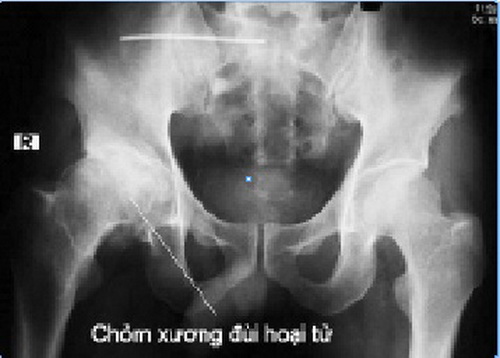

Hoại tử xương: những điều cần biết

07/11/2018

Bài viết tổng hợp những thông tin khái quát nhất về Hoại tử Xương (Hoại tử Vô mạch). Đây là tình trạng bệnh gì? Những nhóm người có khả năng mắc bệnh cao? Bệnh được chẩn đoán như thế nào?... Bên cạnh đó, bài viết cũng mô tả sơ bộ về một số triệu chứng của bệnh